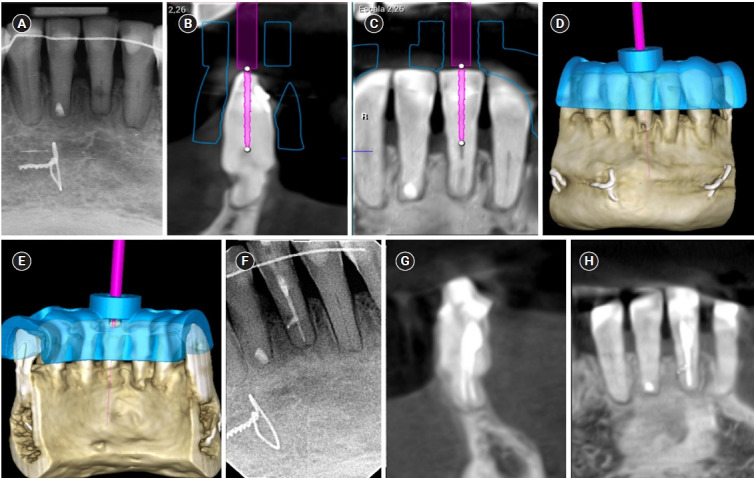

髓室和根管封堵术(PCO/RCO)是非手术治疗的难点。引导牙髓学(GE)旨在精确定位根管(RC)系统,同时尽可能多地保留颈周牙本质。GE包括将受影响牙齿的锥形束计算机断层扫描(CBCT)与上颌/下颌弓的数字印象相结合,允许通过三维(3D)静态导轨仔细规划到RC系统的钻孔路径。本文报告4例PCO/RCO牙伴内外根吸收及水平牙断的病例,均成功应用GE治疗。这些病例强调了使用CBCT进行GE治疗的临床和放射学上的成功,建立了这种技术作为管理矿化牙齿的可预测方法。

Pulp chamber and root canal obliteration (PCO/RCO) presents a challenge for clinicians when nonsurgical endodontic treatment is indicated. Guided endodontics (GE) aims to precisely locate the root canal (RC) system while preserving as much pericervical dentin as possible. GE involves integrating cone-beam computed tomography (CBCT) of the affected tooth with a digital impression of the maxillary/mandibular arch, allowing for careful planning of the drilling path to the RC system through a three-dimensional (3D) static guide. This article reports four cases of teeth with PCO/RCO, accompanied by additional diagnoses of internal and external root resorption and horizontal tooth fracture, all successfully treated with GE. These cases highlight the clinical and radiographic success of GE treatments using CBCT, establishing this technique as a predictable approach for managing mineralized teeth.